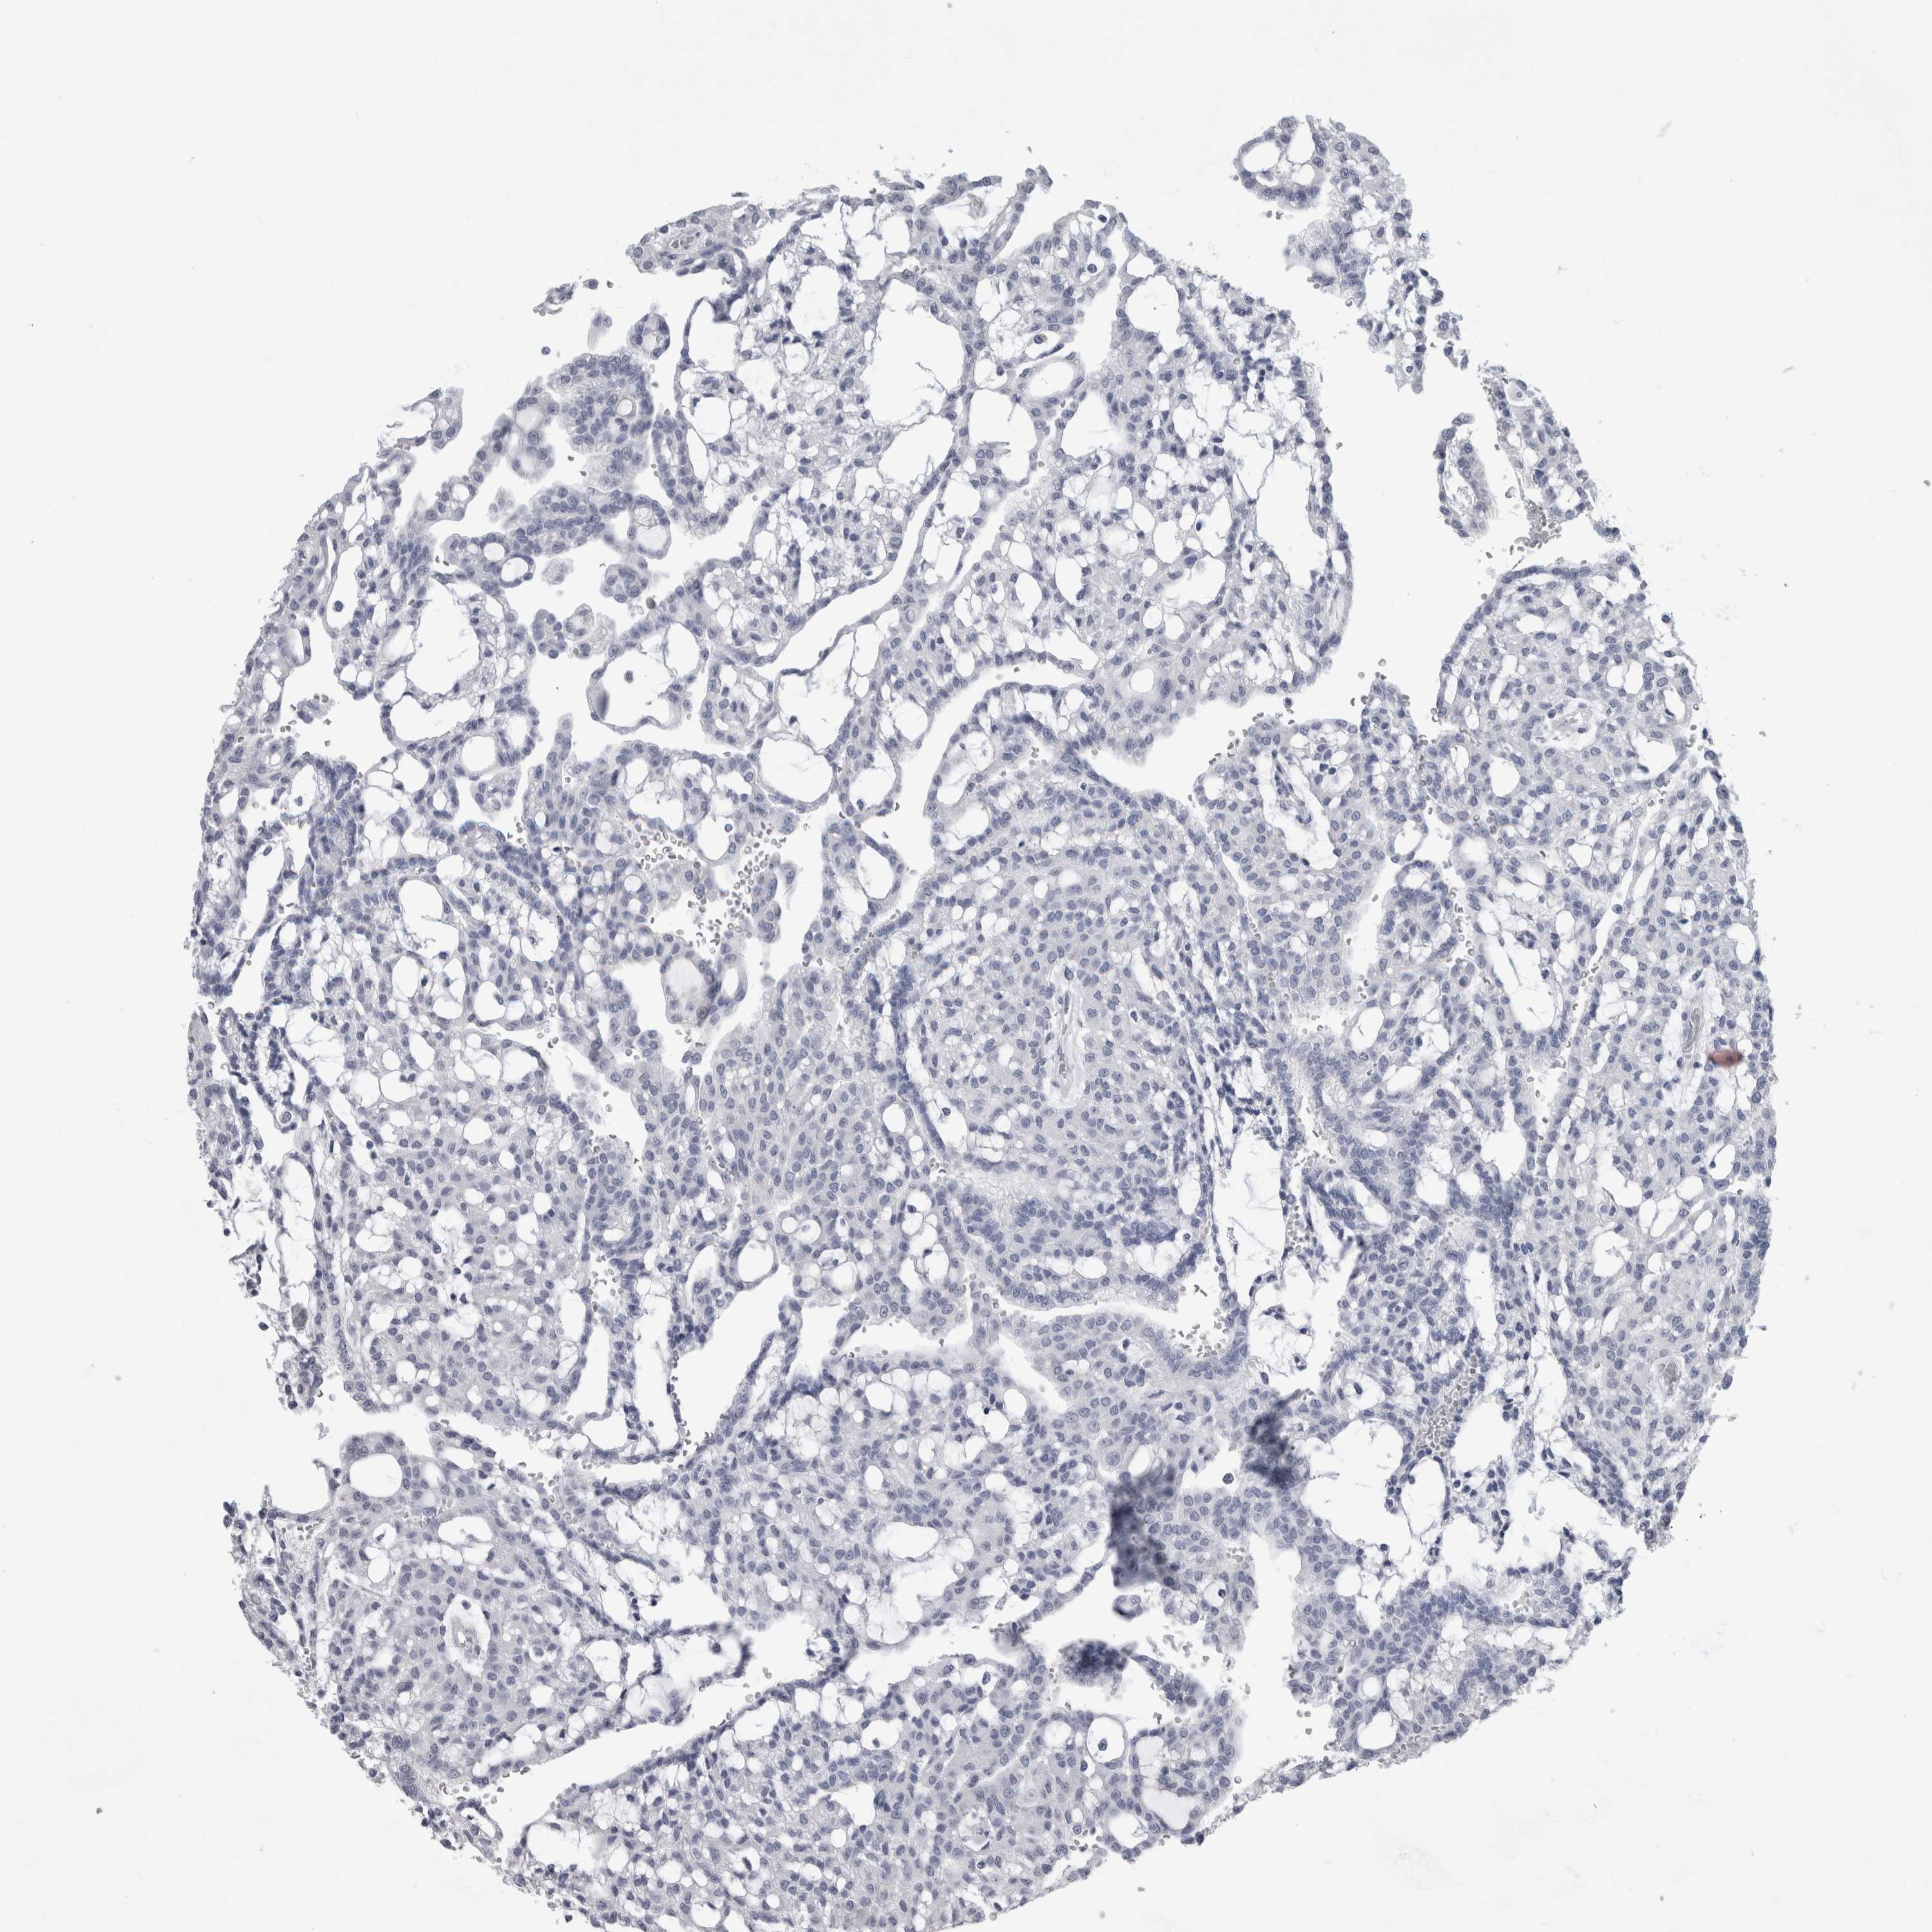

KIDNEY RENAL CLEAR CELL CARCINOMA (VALIDATION) - Interactive survival scatter ploti

The Survival Scatter plot shows the clinical status (i.e. dead or alive) for all individuals in the patient cohort, based on the same data that underlies the corresponding Kaplan-Meier plots. Patients that are alive at last time for follow-up are shown in blue and patients who have died during the study are shown in red.

The x-axis shows the expression levels (FPKM) of the investigated gene in the tumor tissue at the time of diagnosis. The y-axis shows the follow-up time after diagnosis (years). Both axes are complimented with kernel density curves demonstrating the data density over the axes. The top density plot shows the expression levels (FPKM) distribution among dead (red) and alive patients (blue). The right density plot shows the data density of the survived years of dead patients with high and low expression levels respectively, stratified using the cutoff indicated by the vertical dashed line through the Survival Scatter plot. This cutoff is automatically defined based on the FPKM cutoff that minimizes the p-score. The cutoff can be changed by dragging the vertical line or by entering a cutoff value in the square labeled "Current cut-off".

Under the Survival Scatter plot the p-score landscape (black curve; left axis) is shown together with dead median separation (red curve; right axis). Dead median separation is the difference in median mRNA expression between patients who have died with high and low expression, respectively. It is calculated as follows: median FPKM expression of dead patients with high expression - median FPKM expression of dead patients with low expression. This is intended to aid the user in visually exploring custom cutoffs and the associated p-scores and dead median separation.

Individual patient data is displayed and can be filtered by clicking on one or more of the category buttons on the top of the page. Categories describing expression level and patient information include: high, low, alive, dead, female, male and tumor stages. The scale of the x-axis can be toggled between linear and log-scale by clicking on the "x log" button. Mouse-over function shows TCGA ID, patient information and mRNA expression (FPKM) for each patient.

& Survival analysisi

Kaplan-Meier plots summarize results from analysis of correlation between mRNA expression level and patient survival. Patients were divided based on level of expression into one of the two groups "low" (under cut off) or "high" (over cut off). X-axis shows time for survival (years) and y-axis shows the probability of survival, where 1.0 corresponds to 100 percent.

ALDH8A1 is not prognostic in Kidney Renal Clear Cell Carcinoma (validation)

Best expression cut offi

Based on the FPKM value of each gene, patients were classified into two groups and association between prognosis (survival) and gene expression (FPKM) was examined. The best expression cut-off refers the FPKM value that yields maximal difference with regard to survival between the two groups at the lowest log-rank P-value. Best expression cut-off was selected based on survival analysis .

When clicking on this number, the vertical dashed line indicating cut-off, the interactive survival plot, and the Kaplan-Meier curve will be adjusted to show results based on the best expression cut-off.

: 12.96

P scorei

Log-rank P value for Kaplan-Meier plot showing results from analysis of correlation between mRNA expression level and patient survival.

N/A

TCGA RNA samplesi

RNA-seq data is reported as average FPKM (number Fragments Per Kilobase of exon per Million reads), generated by the The Cancer Genome Atlas (TCGA) .

Normal distribution across the dataset is visualized with box plots, shown as median and 25th and 75th percentiles. Points are displayed as outliers if they are above or below 1.5 times the interquartile range. FPKM values of the individual samples are presented next to the box plot.

Average pTPM 30.2

Number of samples 100